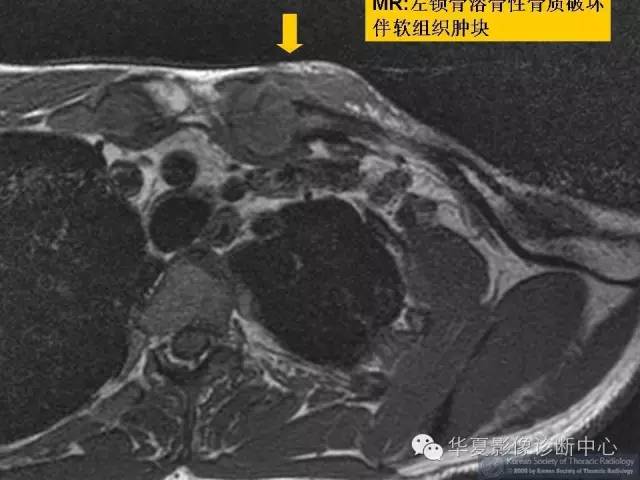

【病例】锁骨结核一例CT及MR影像表现

【病例】锁骨结核一例CT影像表现